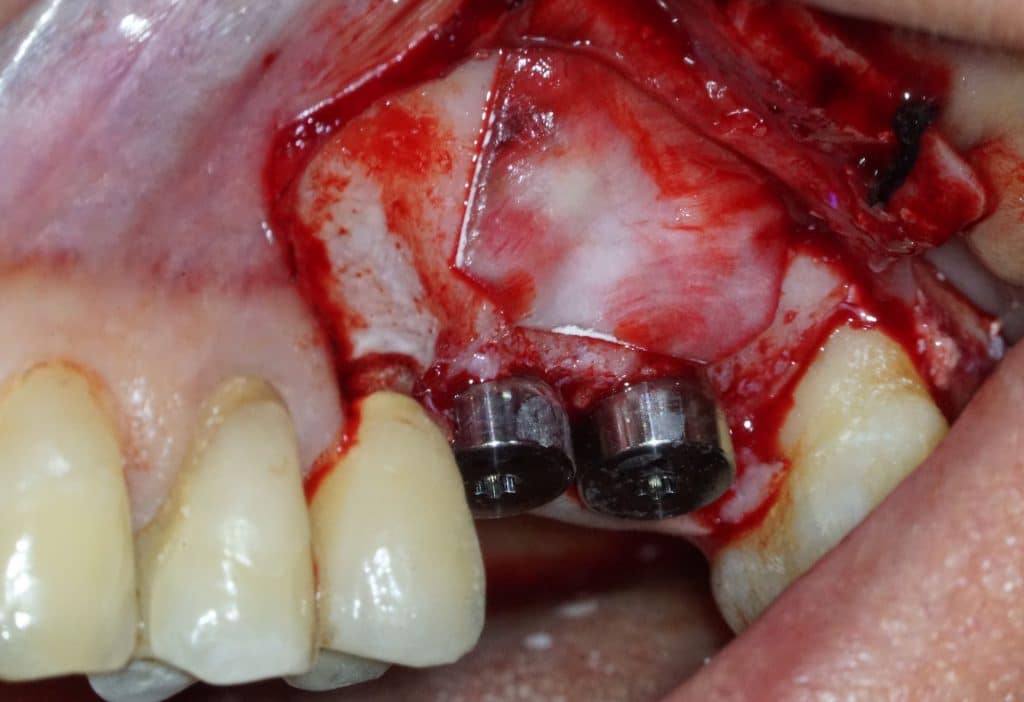

- Two implants are placed drilling the 3 mm of residual crestal bone

- You can see the apexes of the depth indicators inside the maxillary sinus

- Two 8 mm Straumann TLX implants placed

- TLX implants have an excellent primary stability in most cases (as post-extraction cases). But in the case of sinus lift they tend to lose primary stability in the last stages of screwing. Therefore in this case a conical implant is preferable.

- Implants can be seen inside the maxillary sinus through the bone window